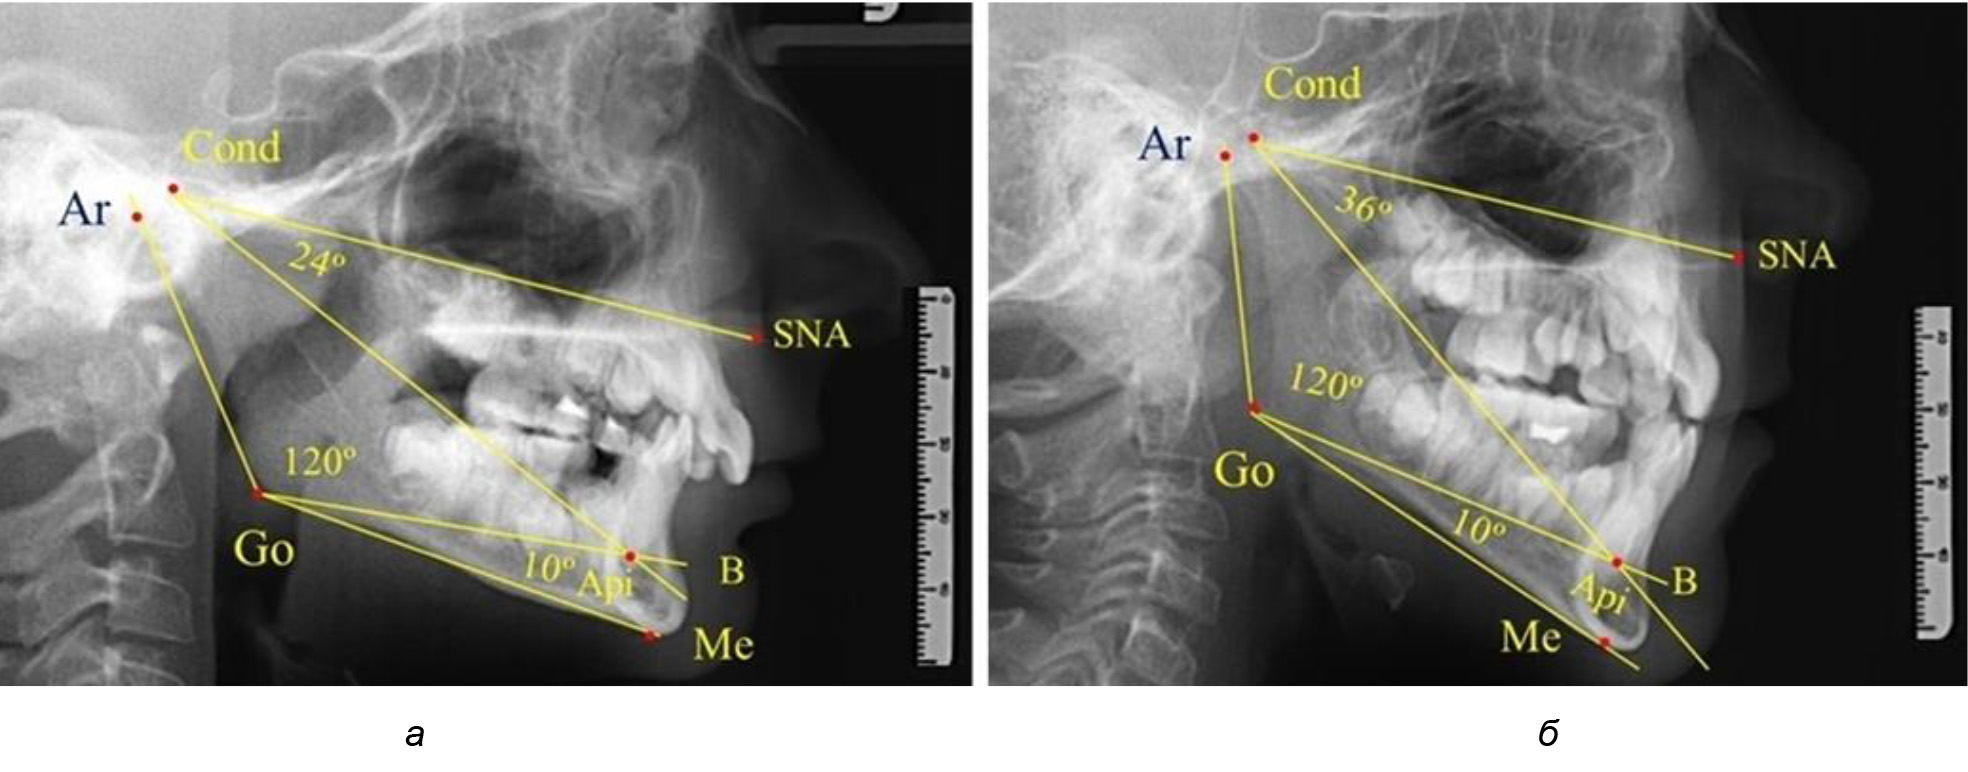

Рис. 1. Расположение реперных точек (а) и линий (б) для оценки угловых параметров гнатической части телерентгенограммы

При анализе ТРГ 5 детей в периоде прикуса молочных зубов отмечено, что величина основного угла гнатической части лица SNA-Cond-Api, как правило, в норме составляла около 30°, и его величина была относительно стабильной у всех обследованных детей. В то же время угол нижней челюсти и его составляющие отличались вариабельностью параметров при различных показателях нижнечелюстного угла (рис. 4).

Рис. 4. Особенности ТРГ (а) и 3D-модели (б) в периоде прикуса молочных зубов

Таким образом, в периоде молочного прикуса с оптимальными окклюзионными соотношениями, несмотря на линейные размеры в вертикальном и сагиттальном направлении, которые, безусловно, меньше параметров взрослых людей, величина основного угла гнатической части лица SNA-Cond-Api соответствовала параметрам людей с полностью сформированным физиологическим прикусом постоянных зубов. Анализируя данные рентгенограмм детей в периоде сменного прикуса, отмечено, что величина основного угла гнатической части лица SNA-Cond-Api, так же как в молочном и постоянном прикусе, в норме составляла от 28 до 32°. В то же время угол нижней челюсти и его составляющие отличались вариабельностью параметров при различных показателях нижнечелюстного угла. Достоверных различий угла гнатической части после смены нижних медиальных резцов и прорезывания первых постоянных моляров (4 ребенка) не было; происходил очередной этап подъема высоты прикуса и увеличение линейных размеров костей гнатической части, однако угловые параметры были относительно стабильны. После смены всех резцов и замены первых молочных моляров первыми премолярами (6 человек) увеличивались линейные размеры при сохранившихся угловых показателях гнатической части лица (рис. 5).

Рис. 7. Варианты ТРГ при глубоком прикусе (а) и при открытом прикусе (б)

На представленных клинических примерах, несмотря на различия параметров основного угла гнатической части лица, определялись однотипные варианты угла нижней челюсти Ar-Go-Me и его составных частей Ar-Go-Api и Api-Go-Me.